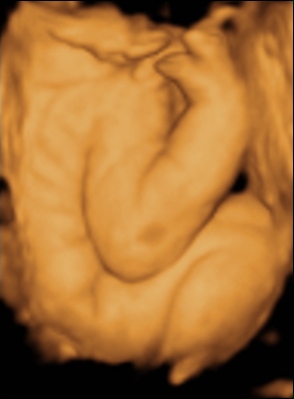

Ma tehát megjártuk a 4D-t meg a cipőboltot. 1,5 órát UHzott a csaj, mert Drága Kistesó nem akarta mutatni magát. Már tornáztam, ettem, ittam épp csak háztömböt nem mentem futni... A végén sikerült 1-2 jobb képet csinálni (azt is csak profilból). Súlya 2 kg (1900valamennyi), mindene 32 hetesnek megfelelő. Minden a helyén van és megvan, hosszú haja van és már most zsíros a Drágám.

No és képek: